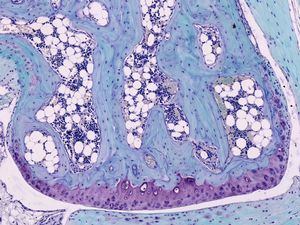

연골은 결합 조직의 일종으로, 세포 외 기질과 그 안에 점재하는 '''연골 세포'''로 구성된다. 세포 외 기질은 '''연골 기질'''이라고 불리며, 콘드로이틴 황산 등의 프로테오글리칸이 주성분이다. 콘드로이틴 황산은 다량의 음전하를 띠고 있어 나트륨 이온과 수분을 끌어당겨 연골이 풍부한 수분을 함유하도록 한다.

연골 세포는 연골 기질 속 '''연골 소강'''이라는 구멍 안에 있으며, 섬유 아세포 계통의 '''연골 모세포'''에서 분화한다. 분열 직후에는 밀집되어 있지만, 주변에 연골 기질을 분비하면서 틈새가 벌어진다. 완성된 연골에서는 하나의 연골 소강에 보통 2~3개의 세포만 존재한다.

연골은 대부분 연골막으로 싸여 있지만, 관절 연골은 예외이다. 혈관은 연골 내부로 침투하지 않으며, 연골 세포는 조직액을 통해 확산 방식으로 산소와 영양분을 공급받고 노폐물을 배출한다.

연골은 연골 기질의 성분에 따라 초자 연골(유리 연골), 섬유 연골, 탄성 연골의 세 종류로 분류된다. 이 세 종류는 엄밀하게 구분되는 것은 아니다.[8]

4. 1. 초자 연골 (유리 연골)

초자(硝子) 연골은 연골질의 수분 함유량이 많고(60-80%), 콘드로이친 황산 등으로 이루어진 콘드롬코이드를 함유하고 있어 압력에 대한 저항력이 강하다. 태아의 골격은 초자 연골로 만들어지며, 순차적으로 뼈로 변해간다. 대부분 성인이 될 때까지 골화(骨化)되지만 늑연골, 비연골, 귀 연골 등은 평생 연골로 남으며, 후두, 기관의 연골이나 관절 연골도 골화되지 않는다.[8]유리 연골은 가장 일반적인 연골로, 관절면을 덮는 관절 연골, 기관이 찌그러지지 않도록 둘러싸는 기관 연골과 갑상 연골, 흉곽의 가동 부분이 되는 늑연골 등이 있다. 유리 연골은 균질하고 무구조이며, 반투명하고 평생 유지되므로 영구 연골이라고 한다. 포유류 태아는 전신 골격이 유리 연골로 나타나 뼈로 치환되며, 출생 후 성장기에는 전신 긴 뼈에 골단 연골(성장 연골)이라 불리는 일시 연골층이 있어 성장에 맞춰 뼈로 치환된다. 이처럼 연골이 대략적인 형태를 만들고 경골로 치환되는 양식을 연골성 골화라고 한다.[9]